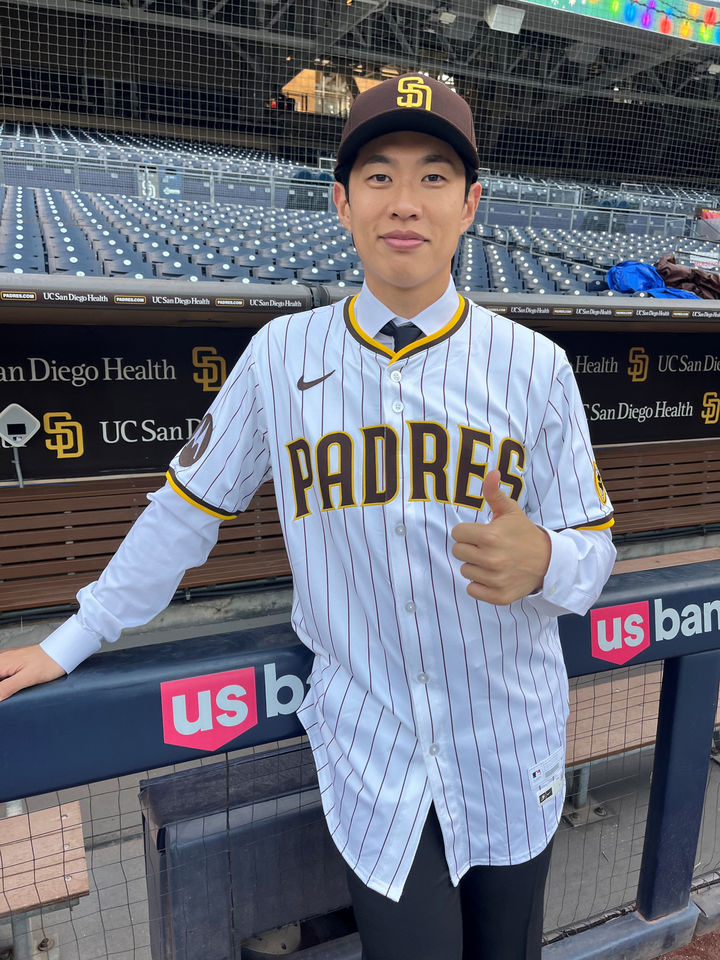

[뉴시스] 엑스레이 촬영 결과 자석이 장 내에서 뭉쳐 인근 조직의 혈류를 차단한 것으로 나타났다. (사진=뉴욕포스트) 2025.10.24.

의료진은 엑스레이 검사에서 그의 장 속에 약 200개의 작은 네오디뮴 자석이 사슬 형태로 뭉쳐 있는 것을 발견했다.

이 자석들은 서로 강하게 끌어당기며 장 벽을 압박해 혈류를 차단했고, 그 결과 장 점막 일부가 괴사했다. 의료진은 자석과 손상된 장 조직을 함께 제거하는 수술을 진행해 소년의 장에서 5×2㎜ 크기의 자석 200여개를 회수했다.